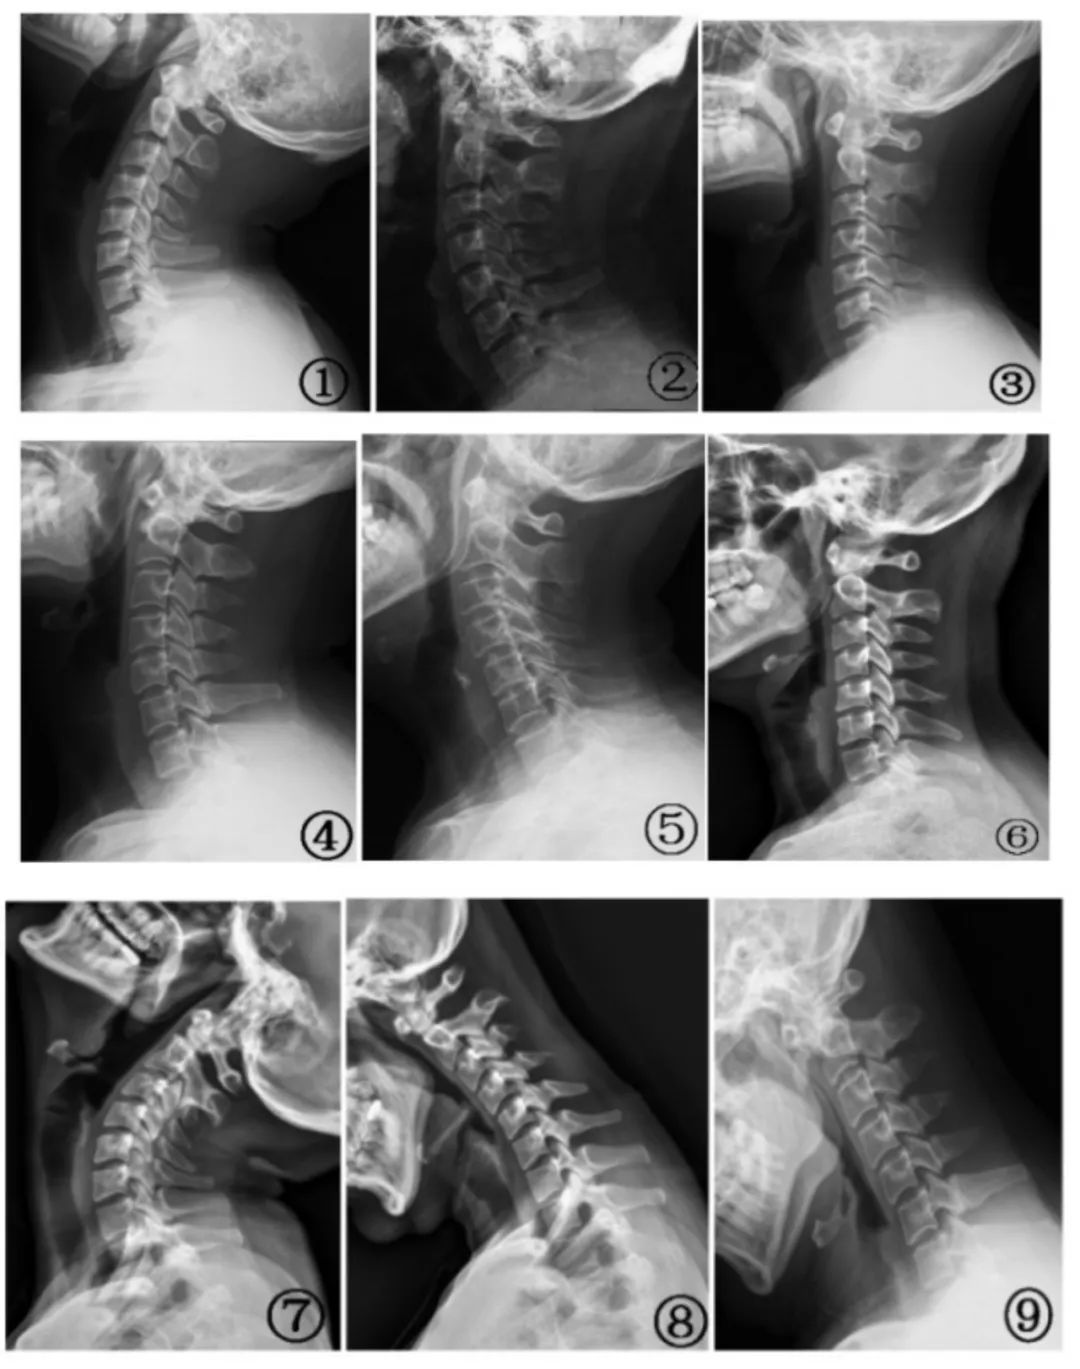

图① 颈椎侧位片;图片② 增加曲度;图表③ 曲率变直;图表④ 曲率变小;图表⑤ 移动弓顶;图片⑥ 轻微反弓;图片⑦ 过伸位颈 4、5 锥水平位移; 图⑧ 锥角速度过曲位中段;⑨ 过曲中下段锥角速度及颈部 5、6 水平位移。图片来自参考文献[1]